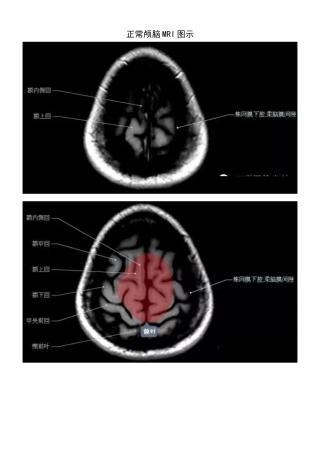

正常颅脑 MRI 图示